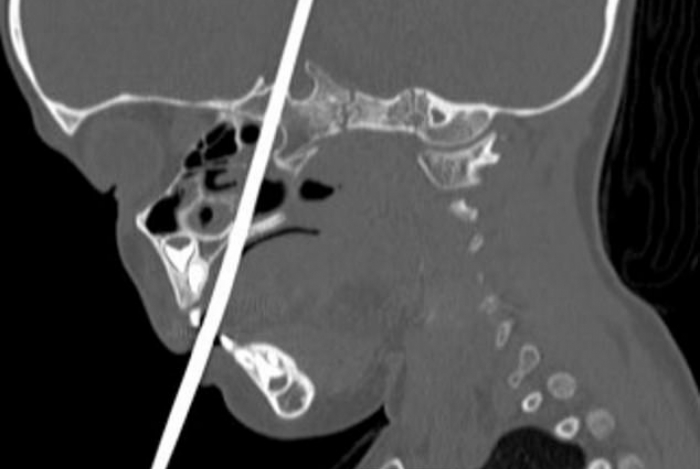

Por mais que ela estivesse sangrando muito, uma tomografia mostrou que os pequenos vasos sanguíneos dela estavam a salvo. A história da “menina mais sortuda do mundo” virou artigo na revista Journal of Pediatric Otorhinolaryngology Case Reports.